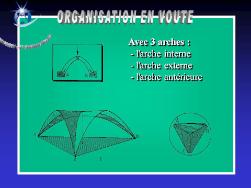

Anatomie du pied

Le squelette du pied est composé de 28 os qui se combinent en de nombreuses articulations.